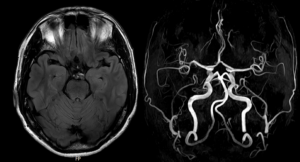

그 사이 대학병원 신경과에서 MRI, MRA,

이비인후과에서 이석증 검사,

내과에서 심전도, 혈액검사도 다 해 봤지만

모두 정상이어서 원인을 알 수 없다고 들으셨다고 합니다.